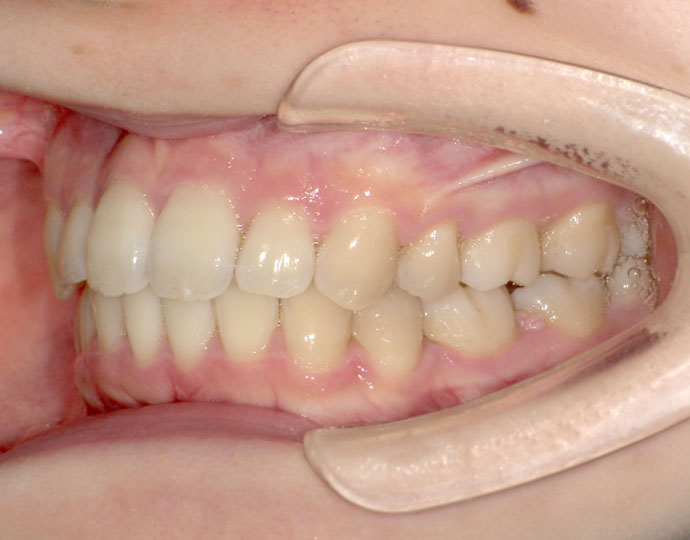

ワイヤー治療 叢生+上顎前突不正咬合 治療例

治療後

治療前後の口元の変化

| 診断 | 叢生歯列を伴う上顎前突不正咬合 |

| 治療方針 | 上顎左右第一小臼歯、下顎左右第二小臼歯の抜歯 |

| 治療に使用した装置 | セルフライゲーションブラケット インプラントアンカースクリュー×2 |

| 治療期間 | 2年6カ月 |